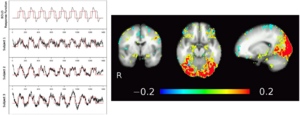

- 3.22 High-field Functional Magnetic Resonance Imaging of Vocalization Processing in Marmosets

- 4.40 Scanning Fast and Slow: Current Limitations of 3 Tesla Functional MRI and Future Potential